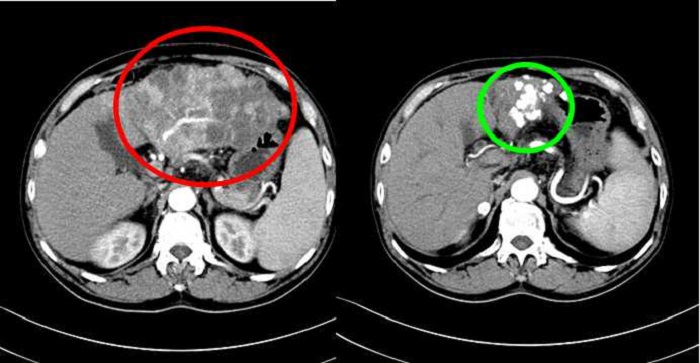

2021-07-22【我為群眾辦實(shí)事】“聯(lián)合”的致勝之路為肝癌患者帶來福...

? ? ? 據(jù)數(shù)據(jù)顯示,每年我國原發(fā)性肝癌新發(fā)病例占世界的一半,絕大部分患者因身體不適就診時,已無外科手術(shù)機(jī)會。而這時介入治療在外科無法切除肝癌的治療中起著主要作用。聯(lián)合靶向治療、免疫治療、放射治療可有效地提高肝癌患者治療效果。? ? ?...閱讀全文